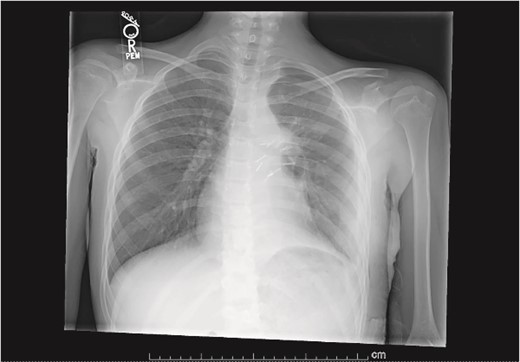

Our patient is a 10-year-old Caucasian female with a history of early adrenarche, ADHD, and COVID-19 and no past surgical history. She presented to the ED with a month-long history of persistent coughing, shortness of breath on exertion and speaking, and left-sided chest pain that began after a diagnosis of mildly symptomatic COVID-19. A physical exam revealed decreased breath sounds on the left, with a left-sided chest protrusion. A plain film and CT demonstrated a normal right lung, with a significant mediastinal shift toward the right, displacement of the heart into the right hemithorax, with complete whiteout of the left hemithorax, and demonstrating a mix of solid and cystic foci, with a round opacification at the left lung base (Figs 1 and 2). The patient underwent an uncomplicated left thoracotomy with excision of two masses, one being 22.5 × 21.0 × 10.5 cm and the other being 13.5 × 11.5 × 6.2 cm. These masses weighed 2394 g in aggregate. The specimens consisted of well-encapsulated tumors attached to the posterior aspect of the chest wall. A regional, positive lymph node measuring 3.0 × 2.2 × 1.0 cm was also resected. Due to the large size of the tumor and the requirement for clean margins, parts of the latissimus dorsi and serratus anterior muscles were also resected. By postoperative day (POD) 0, the left lung had already filled the left hemithorax, and the mediastinal shift had corrected (Fig. 3). The chest tube was removed on POD 5, and a plain film showed continued expansion of the lung to full size and resolving pulmonary edema and atelectasis (Fig. 4). The patient was discharged home on POD 5. The tumor staging was T4N1M0. The tumor was positive for vimentin, CD56, synaptophysin, chromogranin, and NSE. The tumor was negative for pancytokeratin, Cam5.2, EMA, S100, desmin, SMA, SOX10, HMB45, CD117, DOG1, CD99, PR, CD68, WT1, CD30, p53, Alk1, GFAP, and nuclear β-catenin. Next-generation sequencing showed an MGA:NUTM1 fusion, supporting a final diagnosis of high-grade MGA:NUTM1 fusion SCS. Given the size and grading of the tumor, the patient underwent adjuvant CT-RT with ifosfamide, doxorubicin, and proton beam radiotherapy, with supportive doses of MESNA and dexrazoxane for 4.5 months post-operatively. The basis of this treatment is ARST0332 Arm C [6]. Before treatment initiation, the patient underwent an uncomplicated left oophorectomy for reproductive cryopreservation. A PET/CT prior to CT-RT showed hypermetabolic activity in several areas. These included the pleural resection margin, a mediastinal lymph node concerning for metastasis versus postsurgical change, and a left axillary lymph node concerning for metastatic disease. During treatment, the patient contracted human metapneumovirus and rhino/enterovirus, resulting in febrile neutropenia. The patient was successfully treated with blood and platelet transfusions and pegfilgrastim. Upon completion of CT-RT, PET/CT imaging showed no evidence of residual disease, with minimal focal hypermetabolic activity as compared to the previous imaging (Fig. 5).

Plain film showing complete left hemithorax opacification and mediastinal shift (arrows) to right.